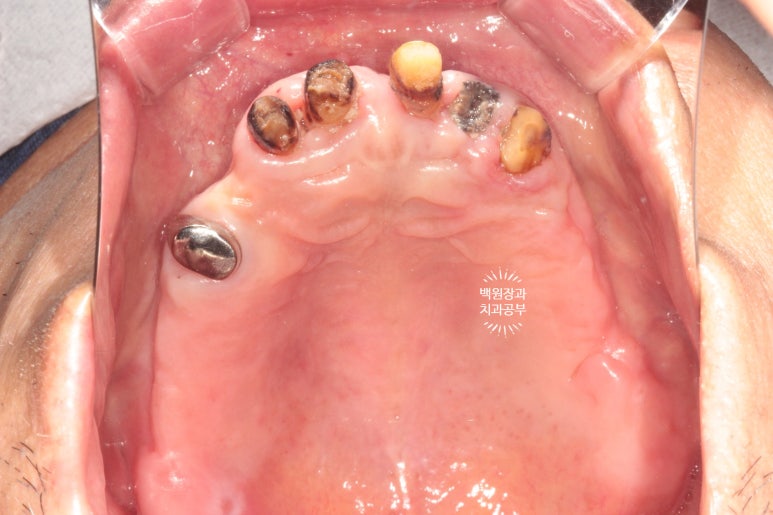

위턱을 보시면 정말로 뿌리만 있는 치아를 보실 수 있어요.

뽑아야 할 위턱 치아는 모두 뽑고,

아래 임플란트 2개는 못쓰니까 제거하고

새 오스템BA임플란트 2개 심어드렸습니다.

짜잔!!! 뿌리만 있던 치아들은 깔끔하게 제거되었고,

건전한 뼈가 있는 곳에 새로이 임플란트 두개를 심어드렸어요.

심고 나니 조금 더 가운데에 심었으면 좋았을텐데... 그치만 앞니 부위는 잇몸뼈의 폭이 너무나 좁았습니다.